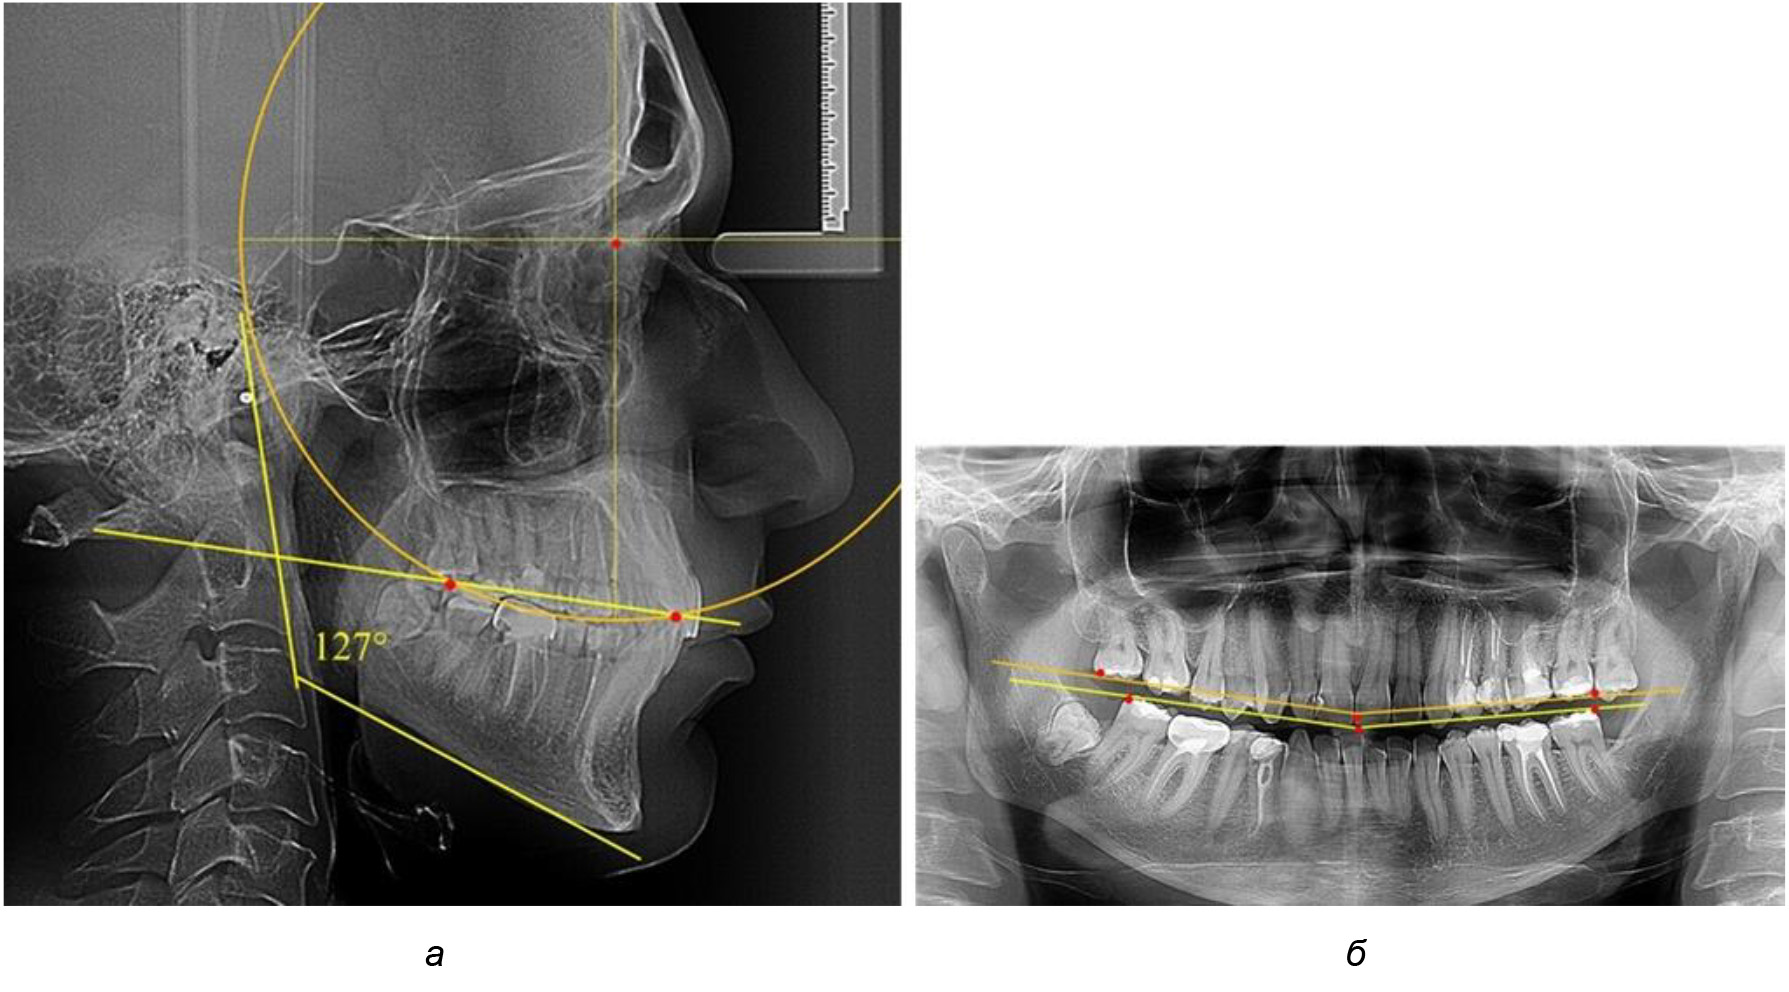

При анализе латеральных ТРГ устанавливали реперный окклюзионные точки в переднем и боковом отделе. Передняя точка устанавливалась на режущем крае нижнего медиального резца, которую в клинике ортодонтии обозначают как vPOcP. Дистальная точка второго нижнего моляра обозначалась как hPOcP. Измеряли расстояние между окклюзионными точками, что определяло сагиттальный размер окклюзионной линии. Использование программ PowerPoint позволило проводить окружность, проходящую по линии смыкания зубов через окклюзионные точки. Измеряли радиус окружности. Учитывая вариабельность размеров окклюзионной линии и радиуса окружности, определяли относительный показатель через отношение радиуса круга к длине сагиттального размера окклюзионной линии. Глубину окклюзионной кривой измеряли от точки наибольшей выпуклости до окклюзионной линии (рис. 1). На ортопантомограмме (ОПТГ) также соединяли окклюзионные точки правой и левой стороны и измеряли глубину окклюзионной кривой от точки наибольшей выпуклости до окклюзионной прямой линии. Результаты глубины кривой Spee сравнивали по данным ТРГ и ОПТГ.

Рис. 1. Метод определения кривой Spee на ТРГ (а) и на ОПТГ (б)

Анализ результатов показал, что глубина кривой Spee в среднем по подгруппе составил (4,12 ± 0,53) мм как при анализе ТРГ, так и ОПТГ.

Деление величины радиуса круга к длине окклюзионной линии составило 1,623 ± 0,02. Таким образом, для определения радиуса окружности, соответствующей кривизне окклюзионного контура боковой ТРГ, необходимо измерить расстояние между передней и задней окклюзионными точками и последующим умножением полученной величины на число Фибоначчи (рис. 2).

Рис. 2. Особенности кривой Spee на ТРГ (а) и ОПТГ (б) у людей с признаками вертикального роста